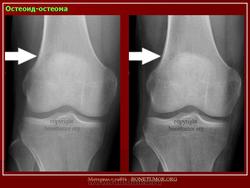

Рентгенологическая картина остеоид-остеомы весьма характерна. Рентгенологические симптомы возникают значительно позже клинических проявлений опухоли, и первым на рентгенограмме обнаруживают склероз кости. На участке поражения формируется одностороннее или муфтообразное утолщение кости в виде гиперостоза. Позднее в толще гиперостоза формируется основной отличительный признак остеоид-остеомы - ее «гнездо» в виде очага разрежения диаметром до 1 см, внутри которого могут отмечаться мелкие костные включения. Сквозь слой склерозированной ткани «гнездо» опухоли на обычных рентгенограммах не всегда дифференцируется и для ее выявления применяют лучи повышенной жесткости и томографию. Обнаружение «гнезда» необходимо для подтверждения диагноза и проведения направленного оперативного вмешательства.